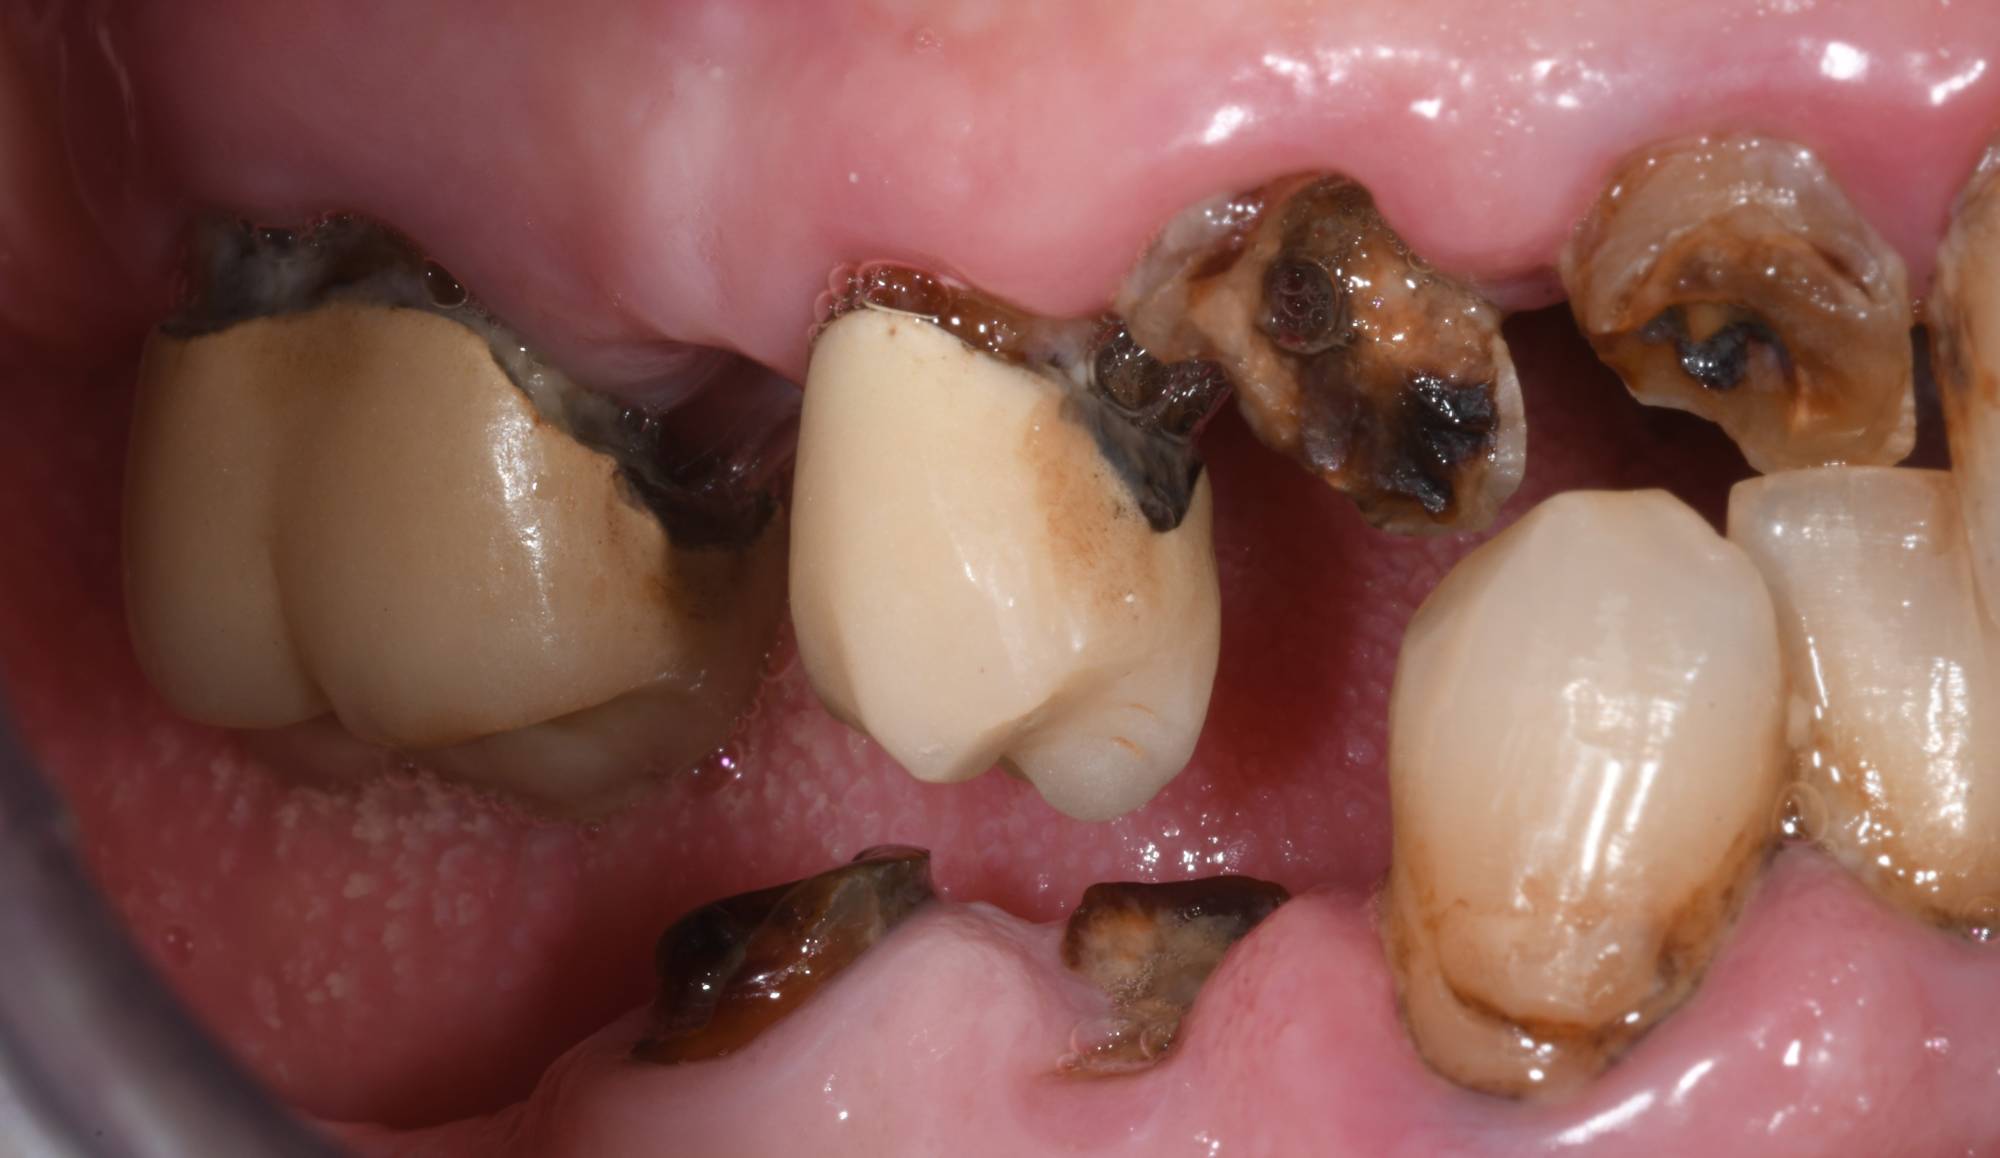

Confronta le foto qui sopra: il paziente necessitava di ripristinare la sua masticazione di destra. Come vedi, nell’arcata superiore aveva vecchie capsule da sostituire e radici da estrarre. Nell’arcata inferiore, due radici da estrarre. Posteriormente era già edentulo, quindi l’unico modo per eseguire una protesi fissa era attraverso quattro impianti, vista l’assenza di pilastri posteriori su cui innestare un ponte fisso.

Superiormente la situazione è diversa. La necessità di mettere delle capsule sui denti naturali suggeriva di sostituire quelli mancanti includendoli in un unico ponte. Tecnicamente degli impianti potrebbero rimpiazzare i denti mancanti, ma visto che i denti vicini vanno comunque incapsulati, appare più sensato optare per un ponte. Questo consentirebbe infatti di ricoprire i denti residui e sostituire i denti mancanti. In questo caso mettere degli impianti sarebbe un “overtreatment”, cioè una terapia non necessaria e più costosa che si può evitare.

Riassumendo, se mancano molti denti e non ci sono pilastri posteriori: impianti. Se ci sono denti naturali residui compromessi e quindi già da incapsulare o con vecchie corone da rifare, meglio un ponte tradizionale.